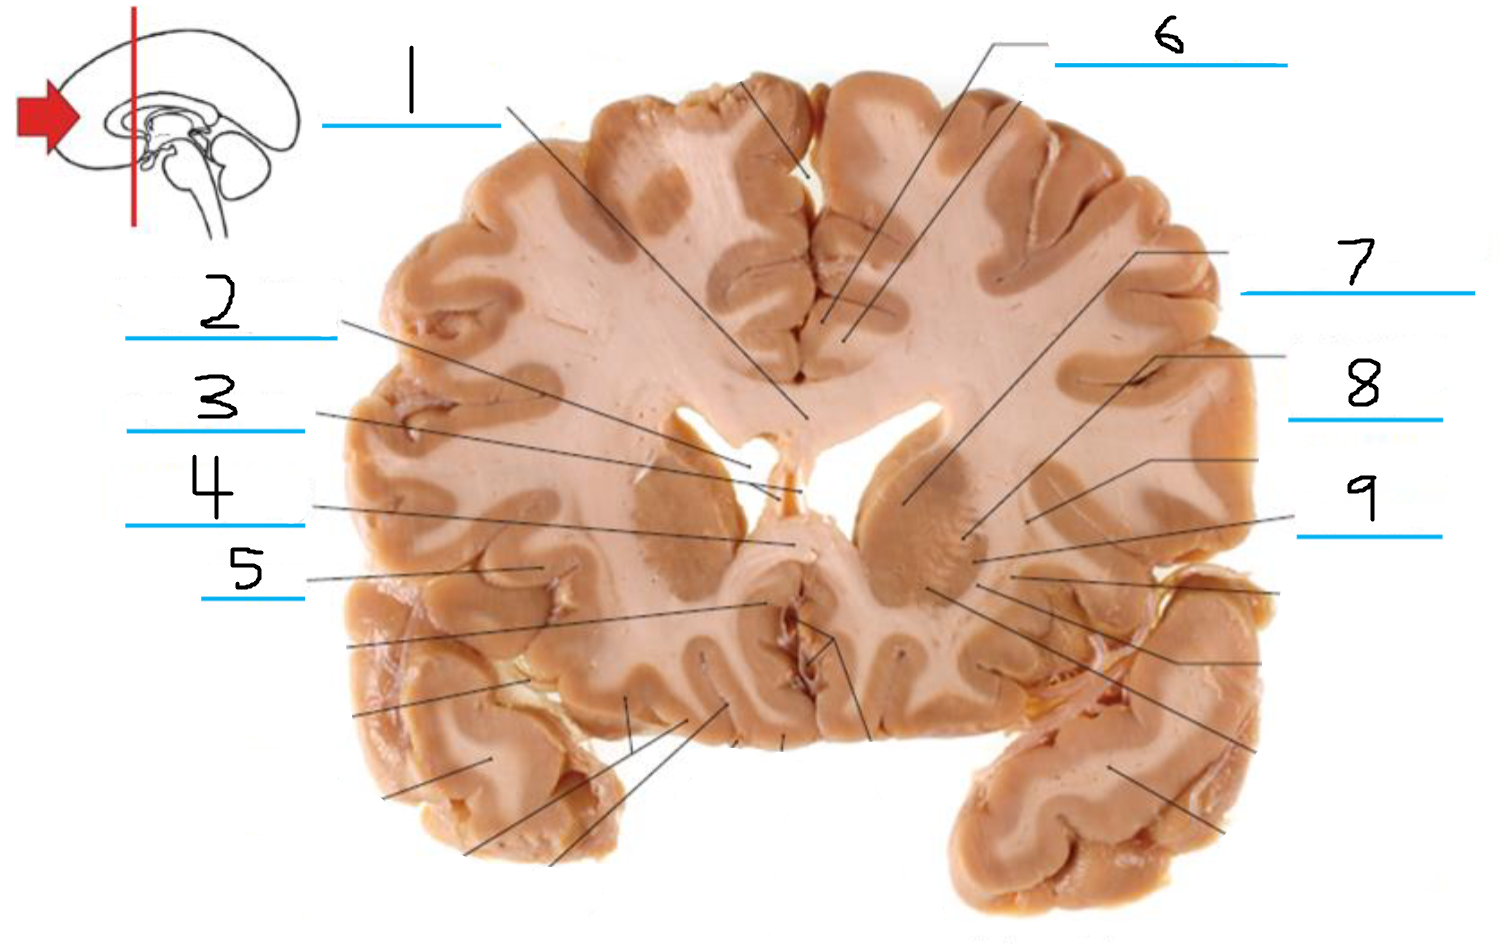

#3 and #16 are the:

Thalamus

#4 is the:

Hypothalamus

#5 and #9 is the:

Hippocampus

#6 is the:

Crus Cerebri

#7 is the:

Basilar Pons

#8 is the:

Mammillary Body

#10 is the:

Caudate

#11 is the:

Third Ventricle

#12 is the:

Globus Pallidus

#13 is the:

Insula

#14 is the

Putamen

#15 is the:

Internal Capsule

#17 is the:

#18 is the:

Lateral Ventricle

#19 is the:

Corpus Callosum